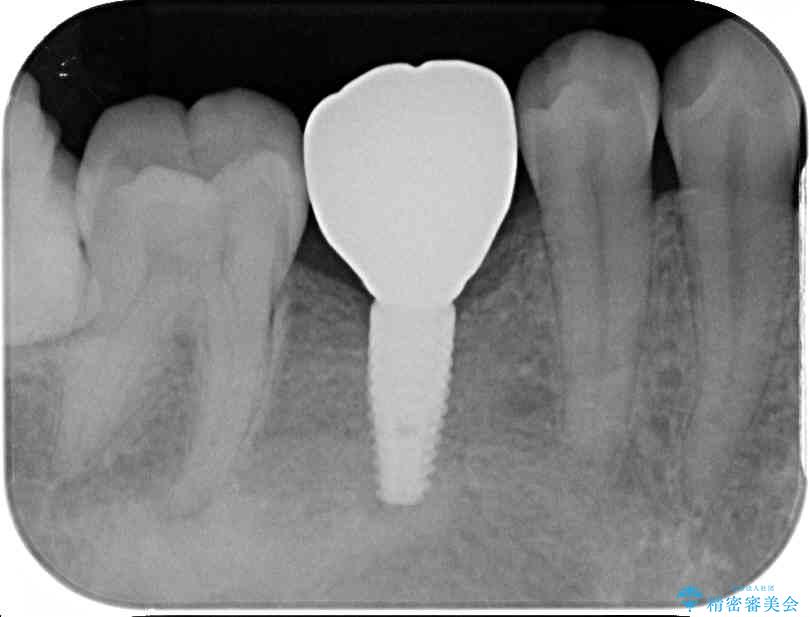

• 空いている時間を利用して通院 奥歯のインプラント治療 治療途中画像